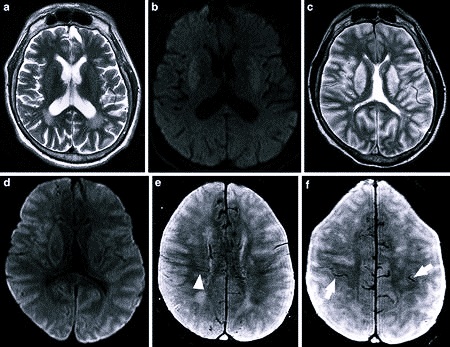

Умеренные диффузные изменения белого вещества головного мозга (БЭА) могут свидетельствовать о различных патологиях, включая сосудистые заболевания, демиелинизирующие процессы и возрастные изменения. Врачи отмечают, что такие изменения часто сопровождаются симптомами, такими как головные боли, снижение когнитивных функций, ухудшение памяти и внимание. Для диагностики используются методы нейровизуализации, такие как МРТ, которые позволяют визуализировать изменения в структуре мозга. Лечение зависит от причины изменений и может включать медикаментозную терапию, физиотерапию и изменение образа жизни. Важно, чтобы пациенты своевременно обращались к специалистам, так как ранняя диагностика и адекватное лечение могут значительно улучшить качество жизни и замедлить прогрессирование заболеваний.

- магнитно-резонансная томография;

На МРТ пациента отправляют, если зафиксирована повышенная электрическая активность. Она свидетельствует о наличии патологии, которая будет заметна на томографическом снимке.